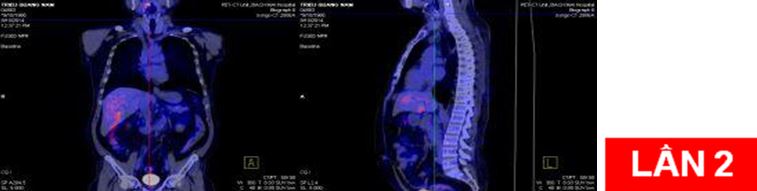

Bệnh nhân:chụp PET/CT lần 2 đánh giá sau 6 chu kỳ hóa chất (có đối chiếu với lần chụp trước khi điều trị).

Sau điều trị: hết u và hạch di căn

Như vậy, bệnh nhân đã đáp ứng tốt sau điều trị với các triệu chứng lâm sàng và cận lâm sàng cải thiện rõ rệt.